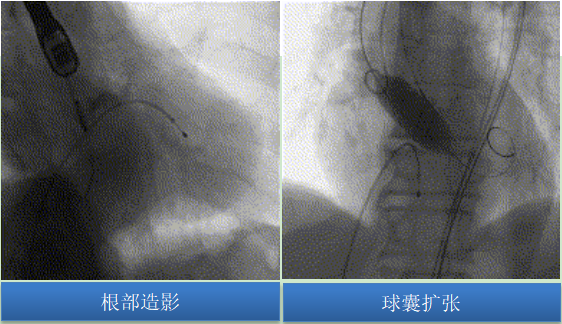

手術(shù)過(guò)程

主動(dòng)脈根部造影可見主動(dòng)脈瓣少量反流,綜合術(shù)前討論竇部結(jié)構(gòu)、左冠風(fēng)險(xiǎn)預(yù)估,采用20mm球囊預(yù)擴(kuò),可以對(duì)瓣膜開放程度及選瓣做正確的指導(dǎo)。術(shù)中未見腰征,無(wú)造影劑滲漏,左右冠顯影良好。

圖片

預(yù)裝TaurusEliteAV26瓣膜,輸送系統(tǒng)順利過(guò)弓、跨瓣,初始于瓣環(huán)平面0mm精準(zhǔn)定位釋放,釋放過(guò)程中瓣膜錨定穩(wěn)定,未下滑。